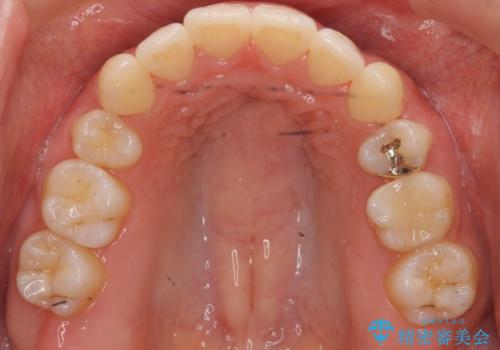

再矯正 昔ワイヤーで治療 前歯の並びを再度きれいに

- 小さいころに小臼歯を抜歯しワイヤー矯正をしたが、すき間が空いてきて、前歯の並びが戻ってしまったとのこと。

インビザラインライトという部分矯正コースで、全体矯正に比べ、比較的安価に治療しました。

前歯の並びが格段にきれいになり、大変喜んでいただけました。